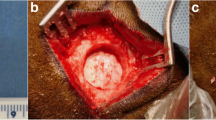

We have evaluated the capability of a collagen/poly glycolic acid (PGA) scaffold in regeneration of a calvarial bone defects in rabbits. 4 bone critical size defects (CSD) were created in the calvarial bone of each rabbit. The following 4 treatment modalities were tested (1) a collagen/PGA scaffold (0.52% w/w); (2) the collagen/PGA scaffold (0.52% w/w) seeded with adipose-derived mesenchymal stem cells (AD-MSCs, 1 × 106 cells per each defect); (3) AD-MSCs (1 × 106 cells) no scaffold material, and (4) blank control. The rabbits were then divided into 3 random groups (of 5) and the treatment outcomes were evaluated at 4, 8 and 12 weeks. New bone formation was histologically assessed. Experimental groups were analyzed by CT scan and real-time PCR. Histological analysis of bone defects treated with collagen/PGA alone exhibited significant fibrous connective tissue formation at the 12 weeks of treatments (P ≤ 0.05). There was no significant difference between collagen/PGA alone and collagen/PGA + AD-MSCs groups. The results were confirmed by CT scan data showing healing percentages of 34.20% for the collage/PGA group alone as compared to the control group and no difference with collagen/PGA containing AD-MSCs (1 × 106 cells). RT-PCR analysis also indicated no significant differences between collagen/PGA and collagen/PGA + AD-MSC groups, although both scaffold containing groups significantly express ALP and SIO rather than groups without scaffolds. Although there was no significant difference between the scaffolds containing cells with non-cellular scaffolds, our results indicated that the Collagen/PGA scaffold itself had a significant effect on wound healing as compared to the control group. Therefore, the collagen/PGA scaffold seems to be a promising candidate for research in bone regeneration.

Hollinger JO, Kleinschmidt JC. The critical size defect as an experimental model to test bone repair materials. J Craniofac Surg. 1990;1:60–8.

Moreira-Gonzalez A, Lobocki C, Barakat K, Andrus L, Bradford M, Gilsdorf M, et al. Evaluation of 45S5 bioactive glass combined as a bone substitute in the reconstruction of critical size calvarial defects in rabbits. J Craniofac Surg. 2005;16:63–70.